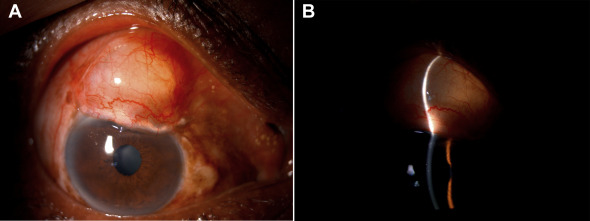

테논낭포(tenon cyst)의 임상양상

테논낭포(tenon cyst)는 특징적인 임상양상을 보이는데,

- 융기된 국소적인 여과포 : elevated localized bleb

- 저명한 표현혈관들 : prominent surface vessel

- 잘개통된 공막누공 내부 patent internal opening on gonioscoy.

즉, 공막누공이 잘열려 있어 안구내부와는 잘연결이 되어 있으나,

안구 외부의 여과포에는, 섬유아세포(fibroblast)의 과형성, 즉 흉터조직의 형성으로 인해서

전방과 직접 연결된 단단한 돔 형태의 얇은 벽으로된 낭포성의 융기가 생기는 것을 말합니다.